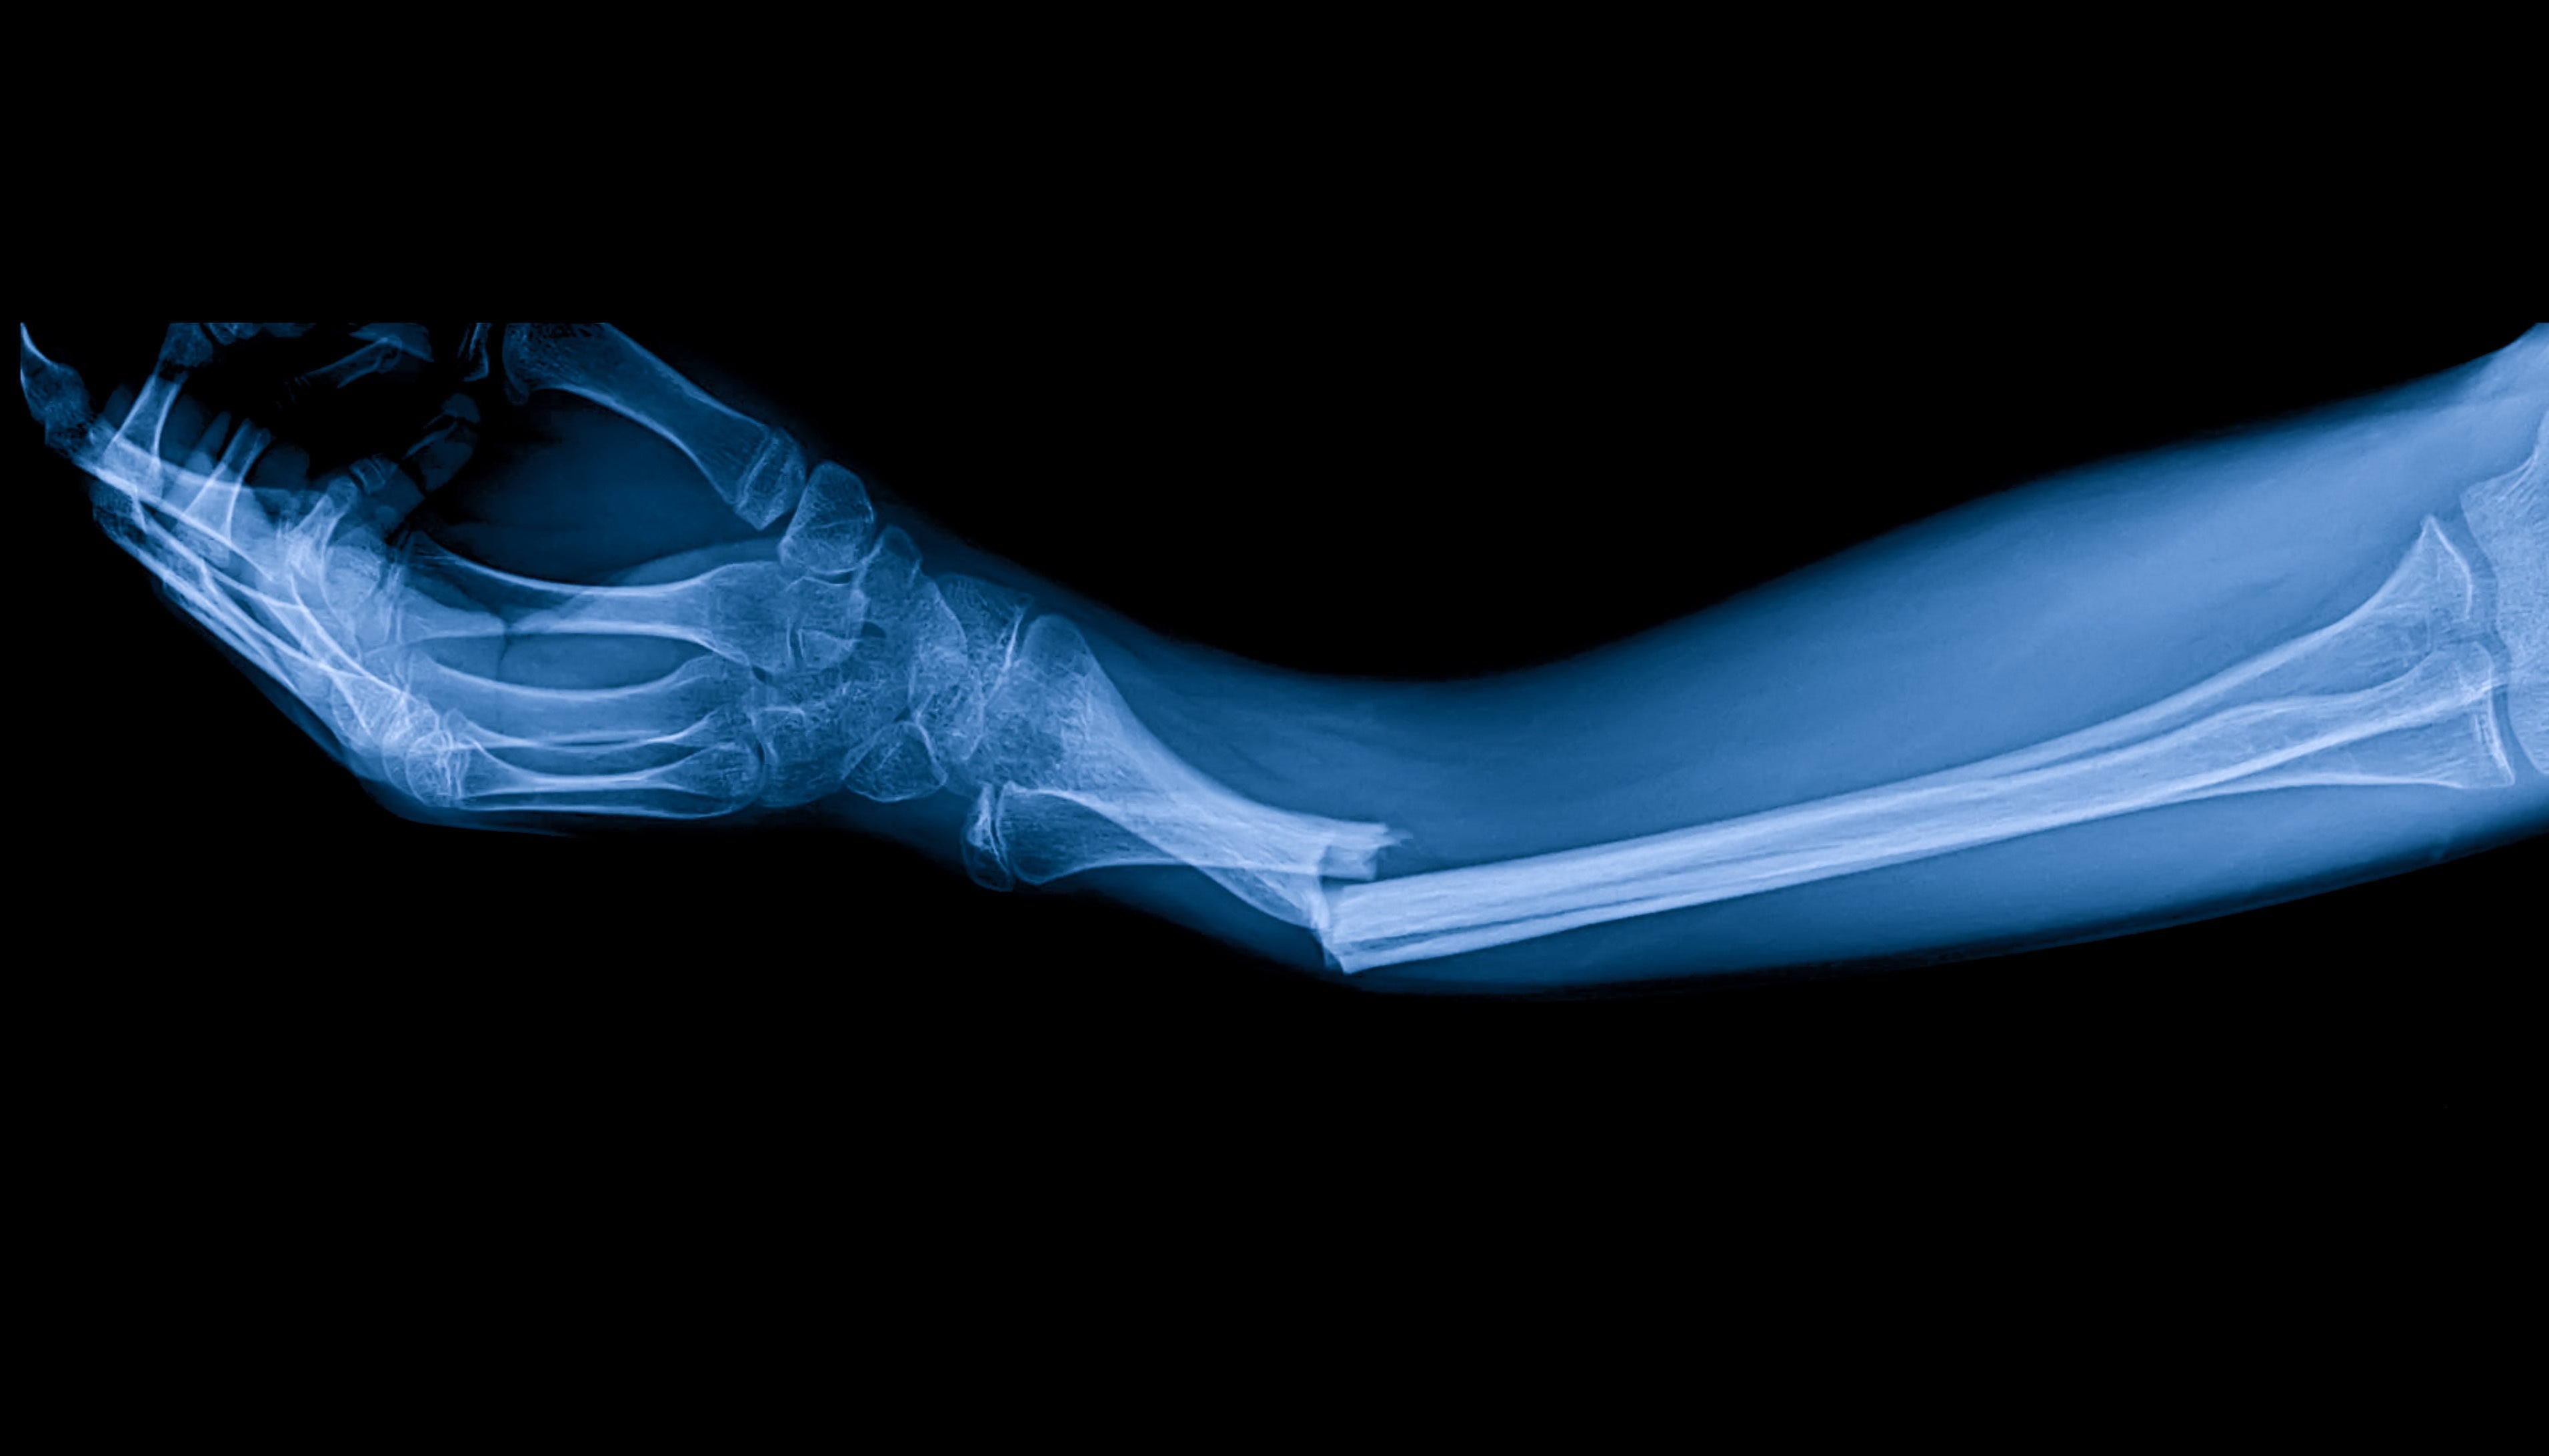

骨折可能是由意外事故、跌倒或运动损伤造成的,根据骨折的严重程度和部位不同,需要相当长的恢复期。传统的骨愈合方法包括使用石膏或夹板固定,有时还需要手术治疗。PEMF 疗法可在分子水平上刺激细胞修复和骨骼生长,是这些方法的补充。